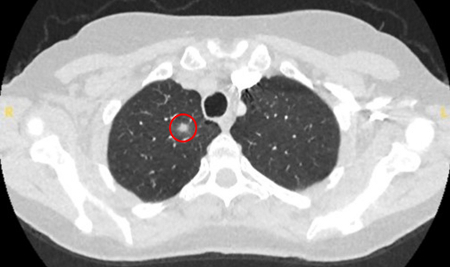

The most likely cause of benign solitary pulmonary nodules will depend on the local epidemiology of disease. For example, at a US academic centre, 23% of patients undergoing resection of a suspicious nodule had benign pathology, with granulomatous disease, such as tuberculosis and fungal infections (e.g., histoplasmosis, coccidioidomycosis, aspergillosis), identified as the most common cause.[10] Non-infectious granulomas are usually due to granulomatosis with polyangiitis (formerly known as Wegener's granulomatosis), sarcoidosis, or rheumatoid arthritis.[Figure caption and citation for the preceding image starts]: Computed tomography (CT) showing a right upper lobe posterior cavitating nodule, with biopsy confirming granulomatosis with polyangiitisFrom the collection of Dr George Tsaknis, MD, PhD, FRCP(London), MRQA, MAcadMEd, PGCert; used with permission [Citation ends].

[Figure caption and citation for the preceding image starts]: Computed tomography (CT) showing a right upper lobe apical solid nodule with a surrounding ‘ground glass’ halo, in a patient with seropositive rheumatoid arthritis on methotrexate. Other similar nodules were seen throughout both lungs, and remain stable for >2 years, consistent with inflammatory benign rheumatoid nodulesFrom the collection of Dr George Tsaknis, MD, PhD, FRCP(London), MRQA, MAcadMEd, PGCert; used with permission [Citation ends].